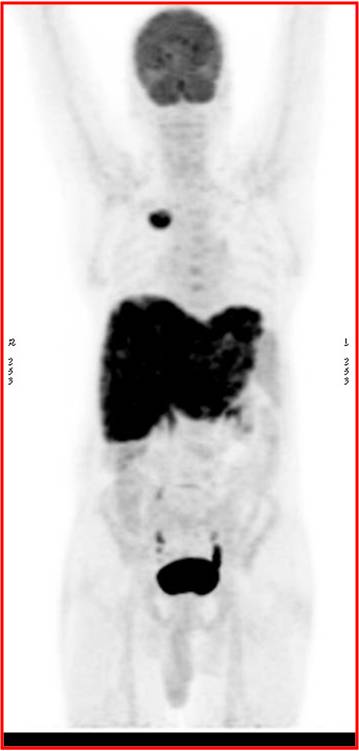

CT scan of the abdomen confirmed the findings ; For further clarification PET whole body scan was done at a centre in Chennai. The following images are from that.

- Metabolically active spiculated right upper lobe lung mass – likely malignant primary.

Mediastinal and retroperitoneal FDG avid metastatic lymphadenopathy.

Extensive FDG avid hepatic metastases involving both lobes.

Focal FDG avid lesion in left lamina of D10 – possibly metastatic.